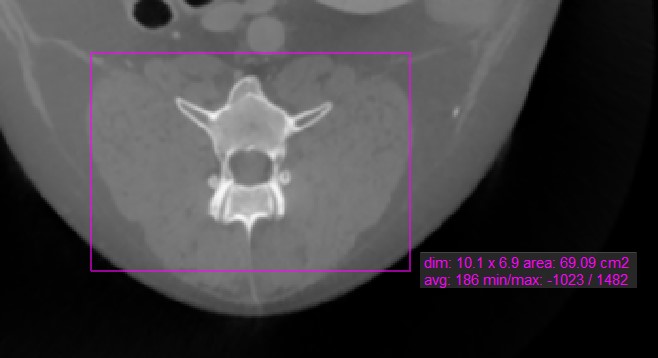

Rectangle

The Rectangle tool offers users the ability to mark a rectangular area on the active image slice.

Select the Rectangle tool and assign it to one of the available mouse buttons. Start the measurement by pressing on the active image slice and drag the mouse to obtain a rectangular shape. Release the mouse when satisfied with the size of the marked area.

All available measurement values are displayed alongside the measurement.

Modify the marked area by moving one of the four points of the rectangular shape using the Default tool.